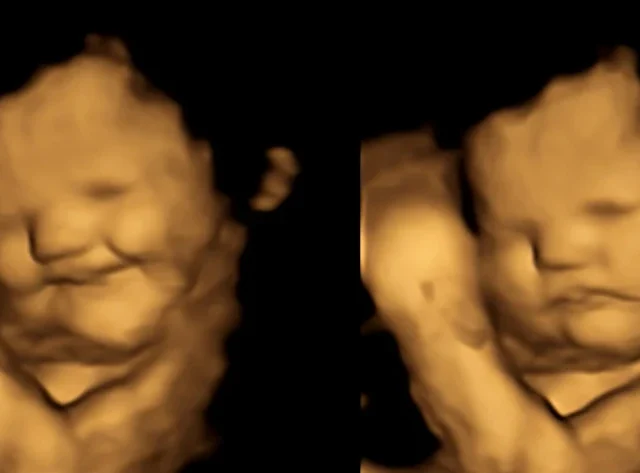

Babies kunnen huilen en lachen ik de baarmoeder

😄 Kunnen baby’s lachen in de baarmoeder? Het korte antwoord is: ja, dat lijkt erop! Hoewel je ze niet kunt horen, is het waar dat baby's in de baarmoeder kunnen huilen en lachen. Onderzoek heeft aangetoond dat baby's leren om...